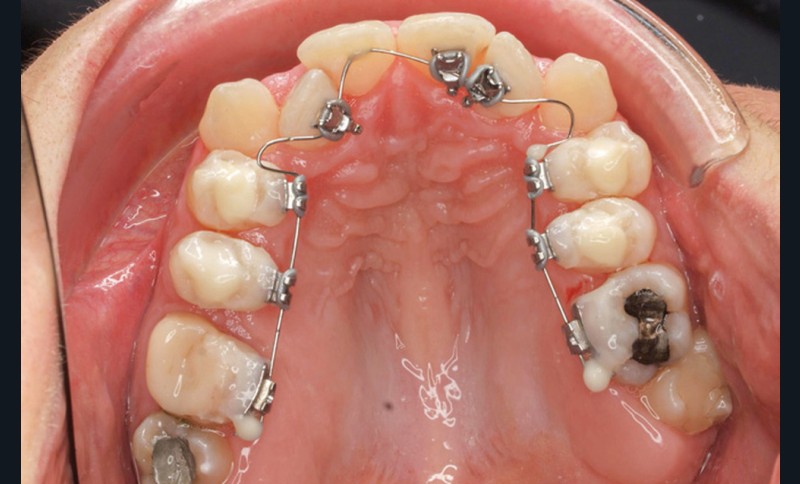

- Premier rendez-vous (fig. 2a) : l’arcade maxillaire est appareillée et un arc NiTi .014 en expansion est placé. L’arcade mandibulaire reçoit des cales rétro-incisives pour lever l’occlusion inversée. Par confort, des cales prémolaires, sans contact avec les dents antagonistes, sont posées pour réduire l’inocclusion latérale.

- Deuxième rendez-vous (fig. 2b) : les dents restantes sont collées et le même arc NiTi .014 est maintenu. Les cales rétro-incisives sont déposées et l’arcade mandibulaire est collée, un arc NiTi 0.014 posé.